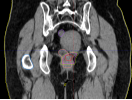

病例展示二:前列腺癌

XXX,男,64岁,主诉:间断性会阴部疼痛10月,确诊为前列腺癌7月。盆腔核磁:前列腺偏左侧异常强化占位,多考虑前列腺Ca,并左侧精囊腺受侵可能,盆腔左侧略大淋巴结。前列腺癌标志物提示:TPSA 88.67 ng/ml,FPSA 3.84 ng/ml。病检:(前列腺穿刺组织左侧)前列腺腺泡腺癌,Gleason评分4+3=7分;(前列腺穿刺组织右侧)Gleason评分3+3=6分。诊断:1、前列腺恶性肿瘤 双侧 腺泡腺癌Gleason评分4+3 =7分 cT3bN0M0 III期 KPS评分:80分。治疗方案:醋酸戈舍瑞林缓释植入剂 10.8mg 皮下注射、比卡鲁胺胶囊 50mg 口服 1次/天”全身治疗,并行前列腺癌碳离子治疗,剂量:57.6 Gy(RBE)/16 Fx。